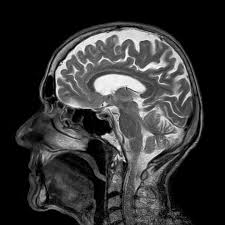

Mri Metal Chair - Magnetic Power Of An Mri Scanner Revealed As It Destroys A Chair In Video Daily Mail Online - The movie. that video is also entertaining, btw.f.. The setup could reach fields up to 13t and the old crt display that accompanied the setup would visibly skew above ~6t (it was pretty close to the magnets). Even in the absence of injury, metal objects can distort the mri image and make it difficult to read. Oct 11, 2014 11:26 am by ben wolford. The tapered back give outstanding lumbar and thoracic support without the bulkiness of a traditional high back. Subscribe today and save $10 on your next order!

4.6 out of 5 stars 4,930. Please see the faq under mri magnet quench: Image resolution improves with 3t mri, so 3t mri is well suited for advanced imaging. View all mri procedure carts; Any metal that enters the mri scan room.

This office chair disassembled itself under the crushing force of the mri magnet. Safety experts have cleared some metals for use during mris. Subscribe today and save $10 on your next order! Image resolution improves with 3t mri, so 3t mri is well suited for advanced imaging. The tapered back give outstanding lumbar and thoracic support without the bulkiness of a traditional high back. Metal wood plastic profit desk 3 4 2 $16 cabinet 9 1 1 $12 chair 1 2 2 $6 if the company has available 810 units of metal, 400 units of wood, and 100 units of plastic, how many desks, cabinets, and chairs should be produced to maximize total profit? The store will not work correctly in the case when cookies are disabled. Even in the absence of injury, metal objects can distort the mri image and make it difficult to read. Mesh back for breathable seating and upholstered fabric seat; So that's why you can't take metal in with you! Mri procedure cart repair parts; Adjustable lumbar support for ergonomic comfort; Metal chair near mri machine (simplyphysics.com) 115 points by mikecapone on june 8, 2010 | hide.

Subscribe today and save $10 on your next order! 4.6 out of 5 stars 4,930. Regarding metal implants before patient is brought into the mri room. Even in the absence of injury, metal objects can distort the mri image and make it difficult to read. This is what happens when one gets careless. The tapered back give outstanding lumbar and thoracic support without the bulkiness of a traditional high back. Even some fabrics contain small amounts of metal, which can cause burns. •ships @ 16 lbs, ups/fedex. 3t mri stands for 3 tesla or the magnetic field strength. When you have an mri, there are strict rules about metal objects. You will be given a locker to store your clothes, and anything else you may have with you during your. That's why we ask all of our patients to change into scrubs for mri exams. These items tested represent many of the important patient support products that are commonly used in clinical mri environments.